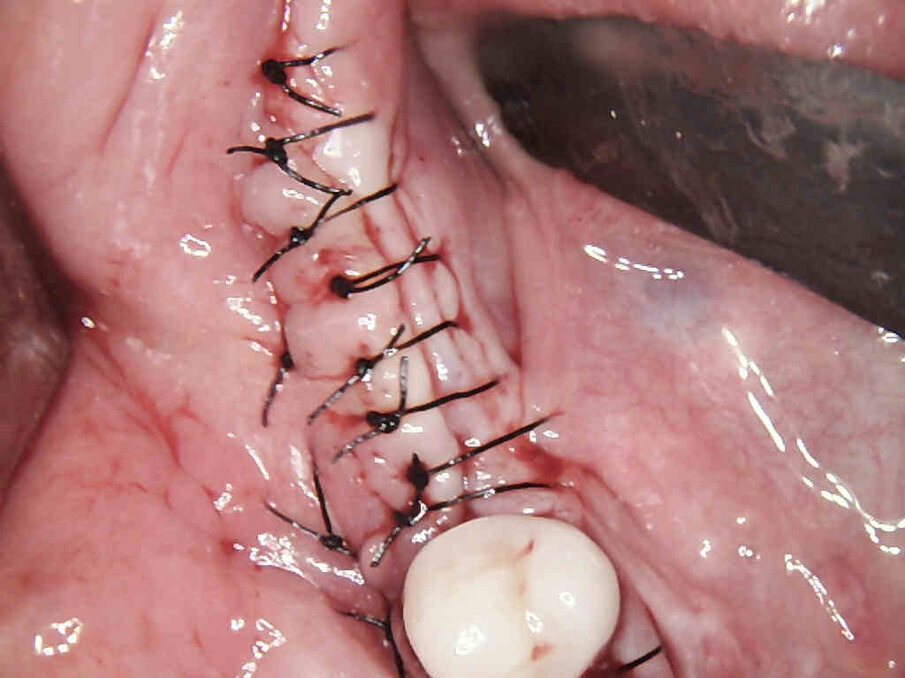

Figg. 7, 8_La membrana Cytoplast viene fissata vestibolarmente ed il lembo viene suturato.